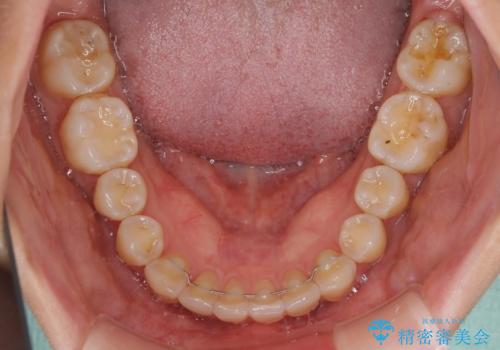

インビザラインによる矯正治療 カリエールディスタライザーを用いた奥歯の咬み合わせ改善

- 前歯の叢生と口元の閉じにくさを気にして来院された患者様です。

奥歯の咬み合わせを見ると、上顎が下顎に対して相対的に前方にありました。

口元の閉じにくさを改善するためには、上顎臼歯を後方に移動させた咬み合わせにする必要があります。

インビザライン単体で改善することも可能ですが、達成する可能性が高くないため、カリエールディスタライザーという補助装置を併用して、より確実性を上げることとしました。

奥歯の咬み合わせを改善しながら、並行してインビザラインで歯列を整えることとしました。

カリエールディスタライザーを併用したことで、確実かつ短期間で治療を終えることができました。